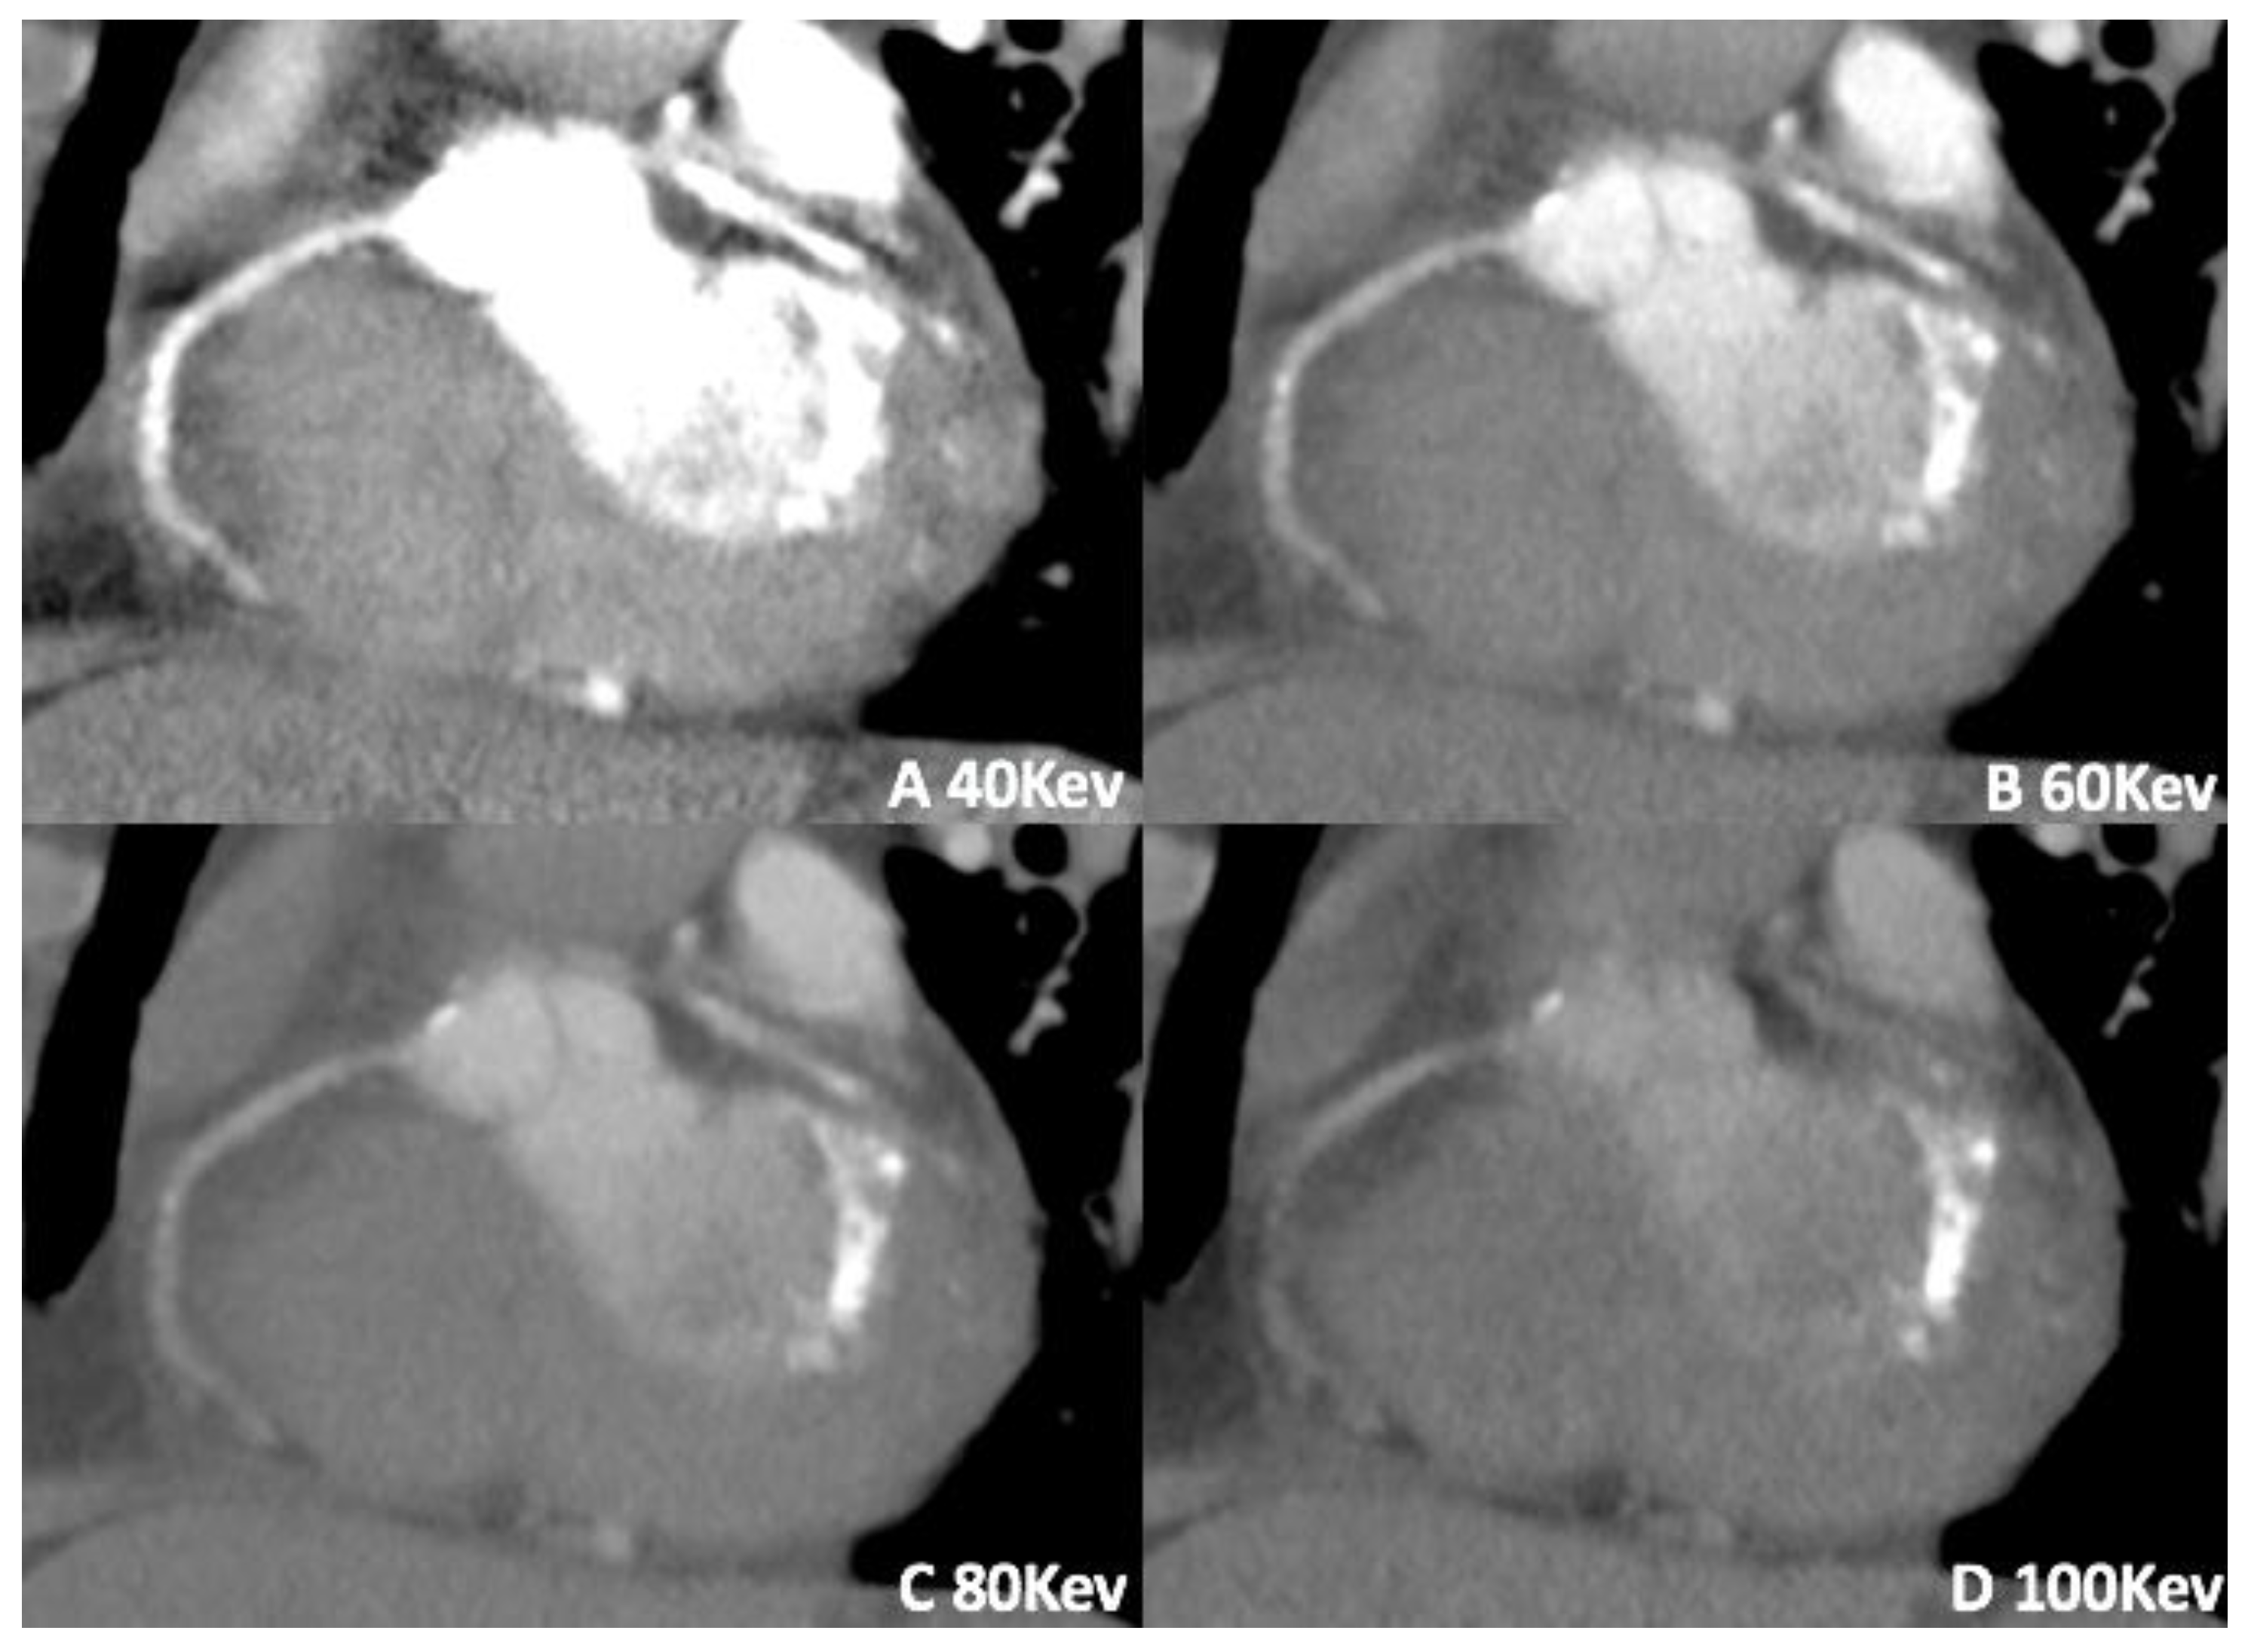

3.3. Virtual Calcium Subtraction

- Allmendinger, T.; Nowak, T.; Flohr, T.; Klotz, E.; Hagenauer, J.; Alkadhi, H.; Schmidt, B. Photon-Counting Detector CT-Based Vascular Calcium Removal Algorithm: Assessment Using a Cardiac Motion Phantom. Investig. Radiol. 2022, 57, 399–405. [Google Scholar] [CrossRef]

- Sartoretti, T.; Eberhard, M.; Nowak, T.; Gutjahr, R.; Jost, G.; Pietsch, H.; Schmidt, B.; Flohr, T.; Alkadhi, H.; Euler, A. Photon-Counting Multienergy Computed Tomography with Spectrally Optimized Contrast Media for Plaque Removal and Stenosis Assessment. Investig. Radiol. 2021, 56, 563–570. [Google Scholar]

- De Santis, D.; Jin, K.N.; Schoepf, U.J.; Grant, K.L.; De Cecco, C.N.; Nance, J.W.; Vogl, T.J.; Laghi, A.; Albrecht, M.H. Heavily Calcified Coronary Arteries. Investig. Radiol. 2018, 53, 103–109. [Google Scholar]